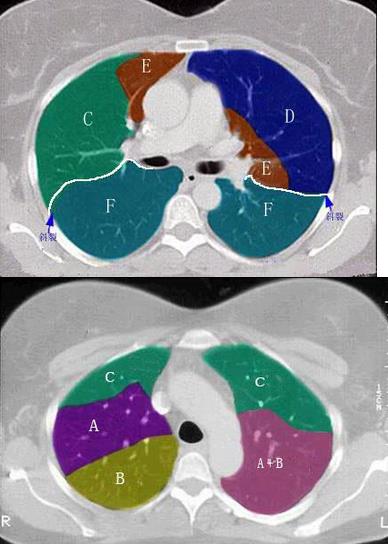

2、 结合肺段模式图,选出右肺中叶的组成()。

• A、B

• B、B+C

• C、B+C+D

• D、D+E

• E、D+E+F